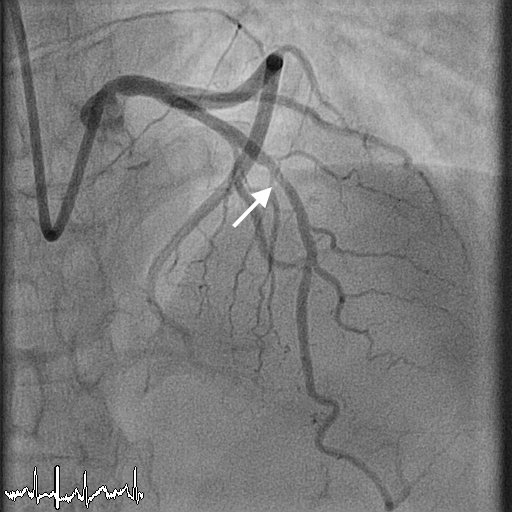

Coronary angiography is a two dimensional visualization (anatomical assessment) of the coronary artery (blood vessels in the heart) by injecting dye inside the heart. The percentage of narrowing or blockage (stenosis) is estimated by direct visualization. When the stenosis is severe (>70%) or mild (<50%) – this estimate will work fine. However, there are situations where the stenosis in the coronary artery is borderline (around 50-70%). During these times, it becomes very difficult to accurately assess the blood flow in that segment to decide on further management (medical therapy/angioplasty with stent/or CABG). FFR is a technique to directly assess the blood flow in coronary artery using a special wire inserted into the coronary artery, which gives us a real estimate of the stenosis to help in decision-making. This is particularly very useful in situations mentioned above. The procedure is similar to angiogram to start with, but uses a special wire, which needs to be inserted in the artery to be tested. This wire will be able to measure the pressure and blood flow inside the blood vessel and thus inform us if there is any compromise in the blood flow.